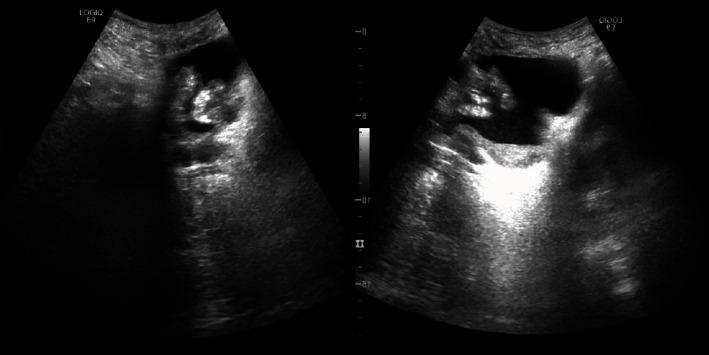

Large cell neuroendocrine carcinoma (LCNC) is one of the rarest types of bladder cancer occurring in <1%. Either pure or mixed with another component, it remains one of the most aggressive types of bladder cancer. We report a case of LCNC of the bladder with an adenocarcinomatous component. The patient was a 64-year-old smoker male, who presented for the first time with dysuria and hematuria. A bladder tumor invading the anterior and right lateral bladder walls was discovered, without any secondary localizations. Tumor biopsy showed an LCNC with adenocarcinomatous components. The patient was treated by recurrent tumor resections, chemotherapy, and radiotherapy. No improvement was noted despite close follow-up and adequate treatment. Neuroendocrine bladder tumor is known to have an aggressive, rapid, and disadvantageous evolution. Multiple case reports were published so far, and a recent review was conducted in March 2020 by Sanguedolce et al. (2020). More cases are needed to establish the best management plan for this type of tumor.

大细胞神经内分泌癌(LCNC)是最罕见的膀胱癌类型之一,发病率低于1%。无论为单纯型还是与其他成分混合型,它始终是最具侵袭性的膀胱癌类型之一。我们报告一例伴有腺癌成分的膀胱LCNC病例。患者为一名64岁男性吸烟者,首次因排尿困难和血尿就诊。发现一个侵犯膀胱前壁和右侧壁的膀胱肿瘤,无任何继发性定位。肿瘤活检显示为伴有腺癌成分的LCNC。患者接受了复发性肿瘤切除术、化疗和放疗。尽管进行了密切随访和充分治疗,但未见改善。已知神经内分泌膀胱肿瘤具有侵袭性、快速且不利的病程。迄今为止已发表了多篇病例报告,Sanguedolce等人于2020年3月进行了一项最新综述。需要更多病例来制定针对此类肿瘤的最佳管理方案。